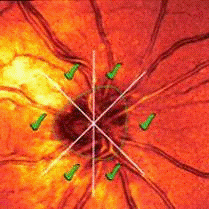

Рис.11 Дефекты в центральной части поля зрения при начальной стадии

глаукомы, выявленные методом кампиметрии: а - парацентральные относительные

скотомы; б - дуговая относительная скотома.

Рис.12 Изменение периферических границ поля зрения при глаукоме

(кинетическая периметрия): а - сужение поля зрения с носовой стороны; б -

концентрическое сужение; в, г - остаточный островок центрального и

периферического поля зрения.